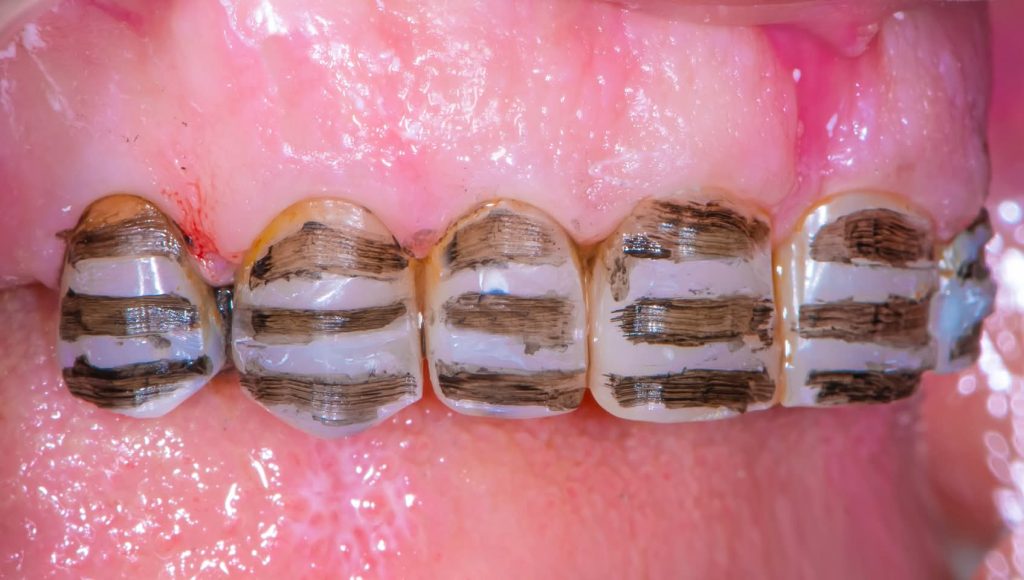

Tooth build-ups to the new vertical dimension of occlusion, aided by the silicone indices.

Preparation of teeth and insertion of the fixed prosthesis.